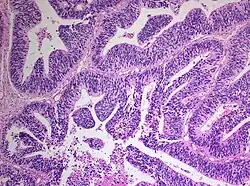

| Histopathology of medulloepithelioma showing characteristic neural tube like strands. | |

Histologically, medulloepithelioma resemble a primitive neural tube and with neuronal, glial and mesenchymal elements.[8][9] Flexner-Wintersteiner rosettes may also be observed.[10]

Immunohistochemically, neural tube-like structures are vimentin positive in the majority of medulloepitheliomas.[11] Poorly differentiated medulloepitheliomas are vimentin negative.